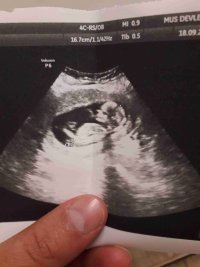

Bizede bakin bu gun verildi doktorumuz erkek dediMerhaba ,

Nub teorisiyle cinsiyeti uzman hekimler belirleyebiliyormuş. Bu yüzden doğruluk payı var.